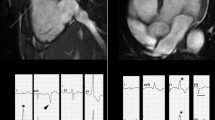

A wide range of manifestations characterizes cardiac sarcoidosis (CS), the most common including complete heart block and right bundle branch block, ventricular arrhythmias and sudden cardiac death [20]. Diagnosis is challenging as ECG abnormalities are shown in just 3.2–8.6% of patients with clinically silent CS [20], and diagnostic criteria include different imaging modalities and histological confirmation [19]. In this setting, CMR represents a useful tool to better characterize myocardial tissue, with a reported negative predictive value of 100%, sensitivity of 100%, specificity of 78%, and diagnostic accuracy of 83% [20]. LGE (Fig. 3) is considered the most useful parameter with a typical mid-myocardial or subepicardial patchy distribution (in some cases it could be subendocardial), revealing areas of myocardial scarring and fibrosis, especially in the chronic phases of CS [21]. A patchy hyperintensity in T2-weighted sequences can be found in patients with active myocardial inflammation [20]. Several studies also showed a significant increase in native T1, T2 mapping and ECV values in patients with biopsy-proven extra-cardiac sarcoidosis as compared with healthy controls [19]. Mapping techniques improve the accuracy of CS diagnostic criteria and represent a helpful strategy to evaluate patients’ response to treatment, since mapping values seem to recover after immunosuppressive therapy in active CS [20]. Although CMR can investigate several aspects of cardiac involvement in sarcoidosis, the diagnosis remains challenging as its different features are often superimposable to that of acute or chronic myocarditis or to myocardial infarction. The novel hybrid imaging techniques like PET-CMR seem promising in the identification of active granulomatous lesions with high sensitivity [22].

57-year-old female with frequent syncopal episodes and ventricular tachycardia, LV dilation and severe reduction in EF at TTE, with no obstruction of coronary arteries at coronary angiography. CMR revealed no edema on T2w-STIR images (a short axis view and d LV long axis view) and extensive areas of late gadolinium enhancement at IR-TFE images (b short axis view and e LV long axis view), with a non-ischemic pattern of distribution. The FDG-PET (c short axis view, f long axis view) confirmed the diagnosis of sarcoidosis with the identification of areas of FDG uptake (i.e., active inflammation) within the myocardium and in the mediastinal lymph nodes. LV left ventricle, EF ejection fraction; TTE transthoracic echocardium

Free-breathing real-time cine sequences are able to depict in CP interventricular septal flattening or bouncing during inspiration. This is related to the pathological ventricular coupling and seems to be more pronounced in the early ventricular filling (Fig. 7) [64], whereas in RCM septal shape does not show any respiratory-related changes [65].

Constrictive pericarditis—TSE T1-weighted images acquired on short axis view before (a) and 3 min after gadolinium administration (b) demonstrate a diffuse thickening of pericardial layer with minimal effusion and slight enhancement of the visceral pericardial layer. On STIR T2-weighted image (c), a focal area on myocardial edema (white arrowhead) is found in the LV inferior wall corresponding to the area of pathological enhancement (black arrowhead) on LGE image (d) by demonstrating a condition of active myocarditis. On free-breathing real-time cine-SSFP acquired in end-expiration (e) and end-inspiration (f), a bouncing and leftward shifting of IVS is seen during inspiration (white arrow) due to the inversion of interventricular pressure ratio combined with inextensibility of the pericardial sac. TSE turbo spin echo; STIR short tau inversion recovery; LGE late gadolinium enhancement; LV left ventricle; SSFP steady-state free precession; IVS interventricular septum